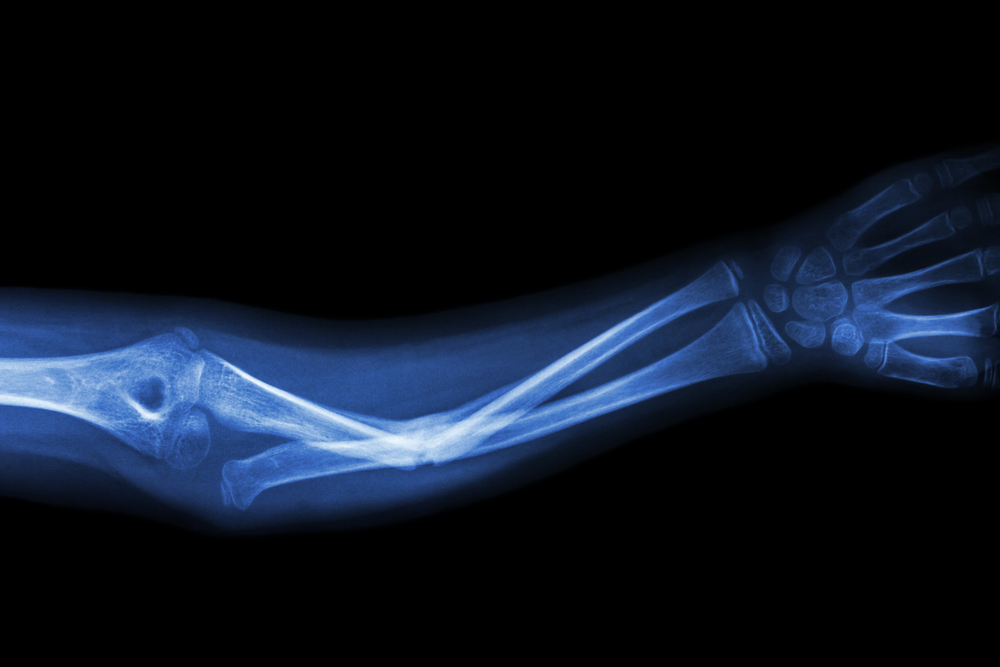

За все время исследования у его участников случилось почти 4 тыс. переломов. Оказалось, что веганы, вегетарианцы и рыбоеды в среднем на 43% чаще страдали от переломов, чем мясоеды. Помимо шейки бедра, сторонники растительных диет в 1,5-2 раза чаще ломали ноги и руки.